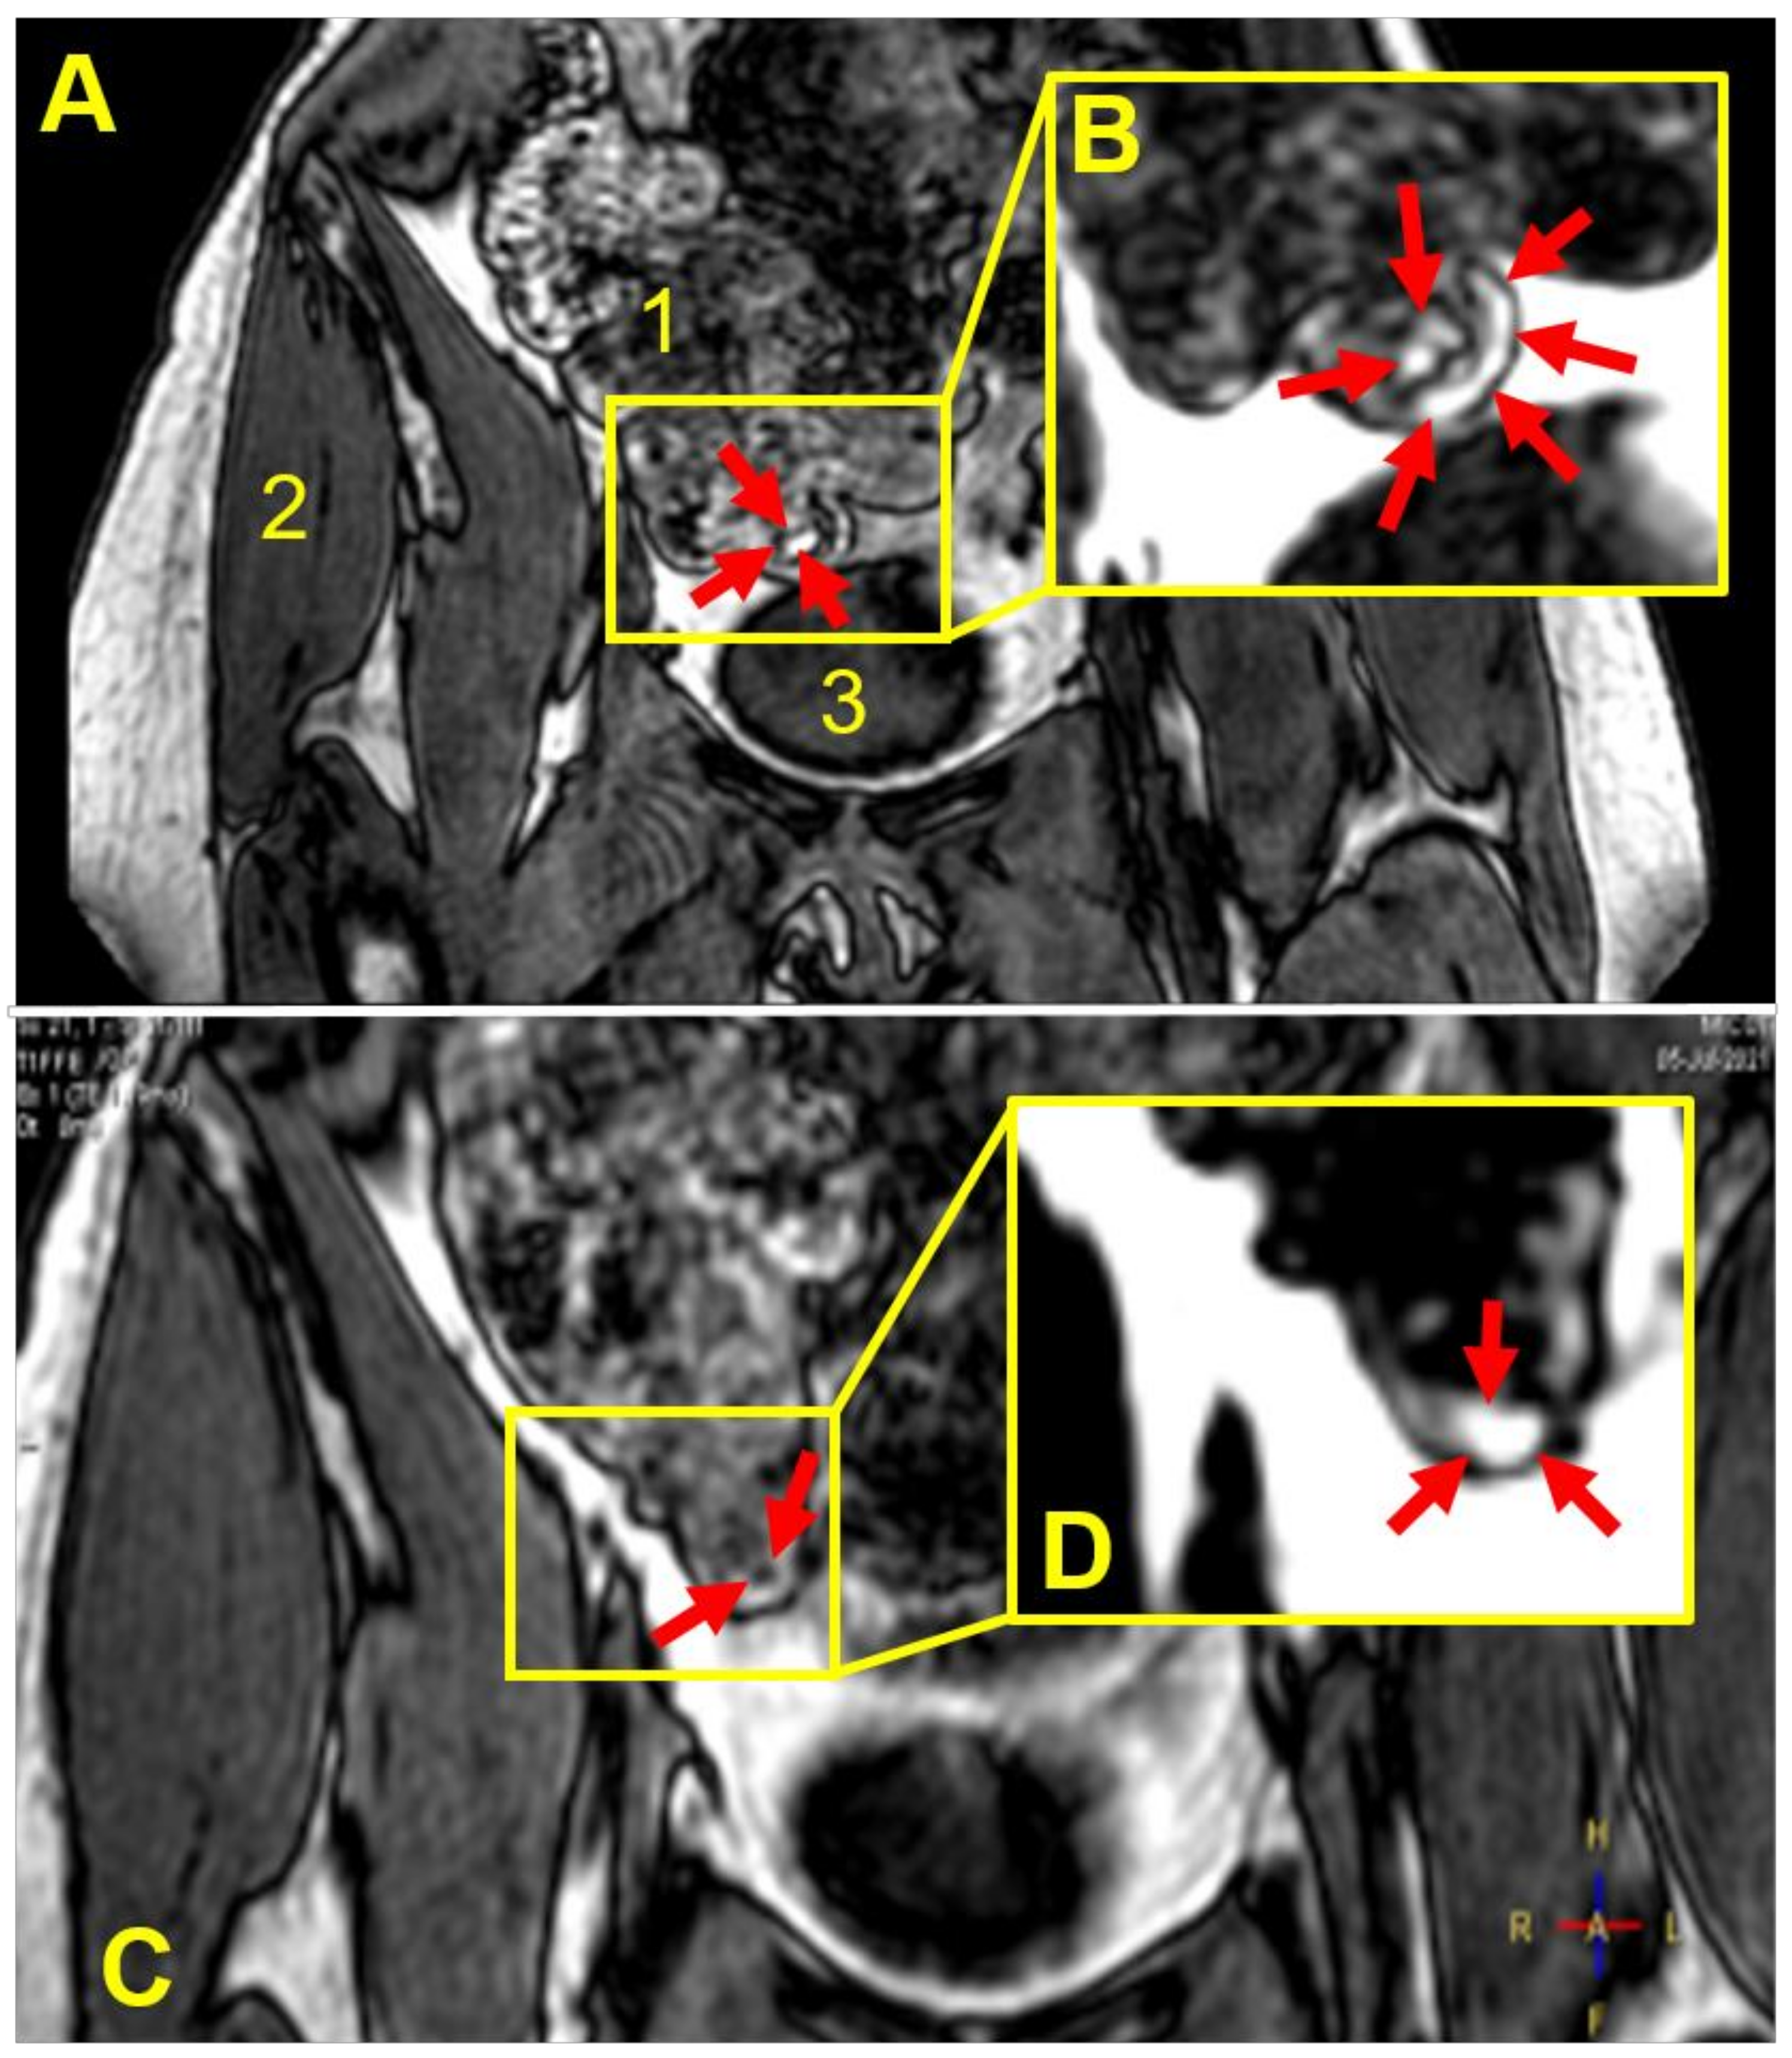

3.3. Capsule Imaging Studies In Vivo

| Participant | Weight Gain (mg) a | Weight Gain Per Surface Area (mg/mm2) | Gastrointestinal Location and Integrity of the Capsule at the Different Imaging Time Points (min) | |||||||

|---|---|---|---|---|---|---|---|---|---|---|

| 45 | 90 | 135 | 180 | 225 | 270 | 315 | 360 | |||

| 1 | 9.2 ± 0.8 | 0.02 | Stomach | Stomach | Stomach b | NO c | NO | NO | NO | NO |

| 2 | 18.2 ± 1.2 | 0.04 | Stomach | Stomach | Duodenum | Duodenum | Term ileum | NO | NO | d |

| 3 | 18.2 ± 1.2 | 0.04 | Stomach | Stomach | Term ileum | Asc colon | Hep flexure | Hep flexure | Hep flexure | Hep flexure |

| 4 | 18.2 ± 1.2 | 0.04 | Stomach | Jejunum | Jejunum | Jejunum | Term ileum | Term ileum | Term ileum | NO |

| 5 | 18.2 ± 1.2 | 0.04 | Stomach | Jejunum | Cecum | Cecum | Asc colon | Asc colon | NO | Hep flexure |

| 6 | 18.2 ± 1.2 | 0.04 | Stomach | Stomach | Term ileum | Term ileum | NO | NO | NO | NO |

| 7 | 18.2 ± 1.2 | 0.04 | Stomach | Jejunum | Jejunum | Term ileum | Term ileum | NO | NO | NO |

| 8 | 36.0 ± 5.2 | 0.08 | Stomach | Jejunum | Term ileum | Cecum | NO | NO | shade | |

| 9 | 52.6 ± 9.7 | 0.11 | Stomach | Duodenum | Term ileum | Hep flexure | Hep flexure | Trans colon | Trans colon | |

| 10 | 52.6 ± 9.7 | 0.11 | Stomach | Stomach | Duodenum | Duodenum | NO | NO | ||